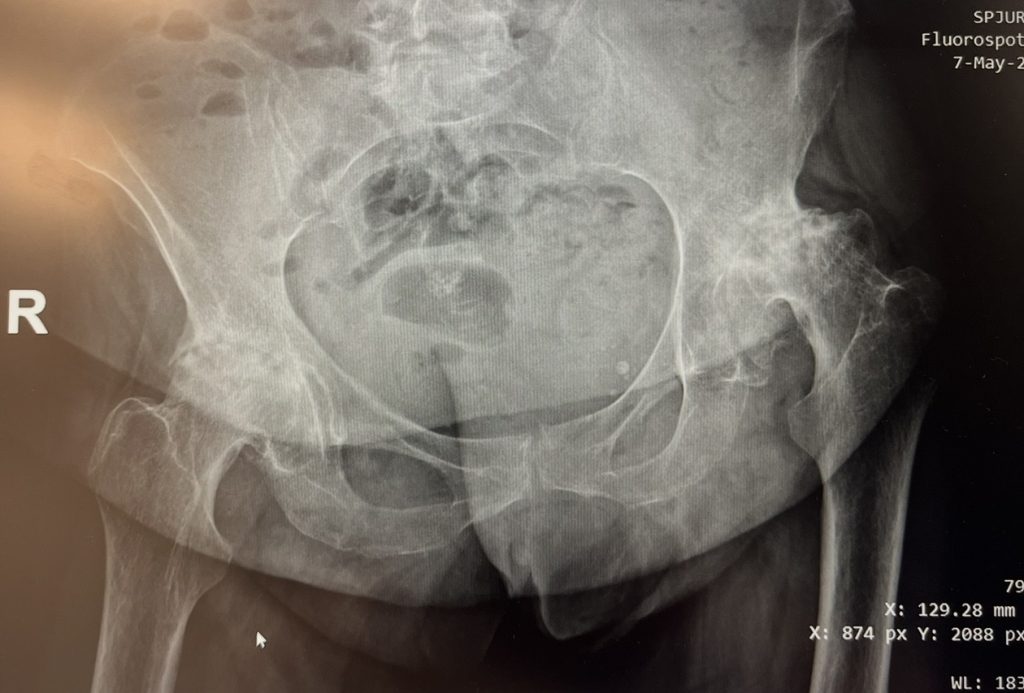

Pacienta, în vârstă de 56 de ani, s-a prezentat cu displazie coxală severă la șoldul stâng și coxartroză avansată la șoldul drept, asociate cu o scurtare a membrului inferior de aproximativ 2 cm.

După o evaluare atentă și planificare chirurgicală individualizată, am decis efectuarea unei artroplastii totale de șold bilateral, în doi timpi operatori, la un interval de aproximativ două luni între intervenții.